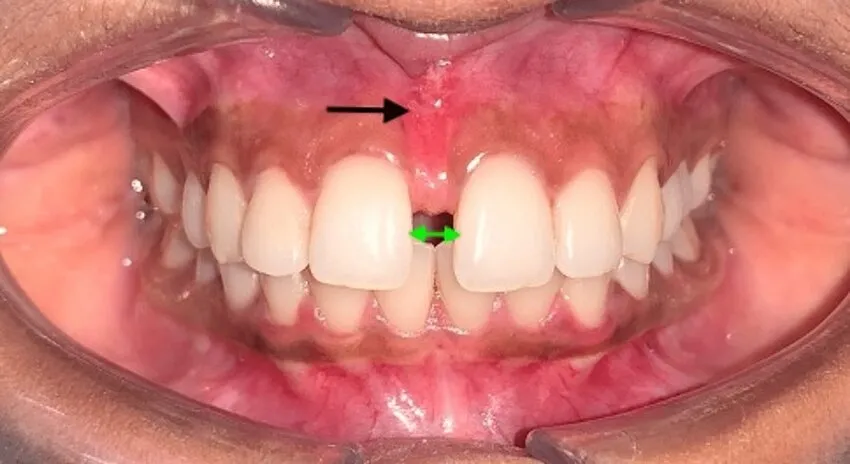

• Frenotomy: A quick procedure to release a tight frenulum (tongue-tie or lip-tie), improving speech, feeding, or oral function with minimal discomfort.

• Midline Diastema Closure: Laser-assisted treatment to close gaps between front teeth, enhancing aesthetics and function with precision.